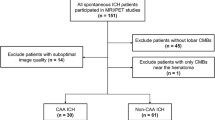

Of the 215 patients, 41 had single lobar or strictly deep CMBs and 89 had no CMBs, so 85 patients with multiple (≥ 2) lobar CMBs were included in the final analysis. Those who were excluded were not significantly different from those included in the analysis except for the average MMSE score and the prevalence of hypertension (Table 1). Among the 85 patients with multiple (≥ 2) lobar CMBs, 41 (48.2%) patients showed probable-CAA and the remaining 44 (51.8%) patients showed mix-CMBs. The clinical characteristics of the 85 patients are shown in Table 2. CMIs were detected in 9 of the 41 (22.0%) patients in the probable-CAA group, and 12 of the 44 (27.3%) patients in the mix-CMB group (p = 0.57). A flowchart of the patient selection is shown in Fig. 1. Representative images of CMIs from one patient each in the probable-CAA and mix-CMB groups are shown in Fig. 2.